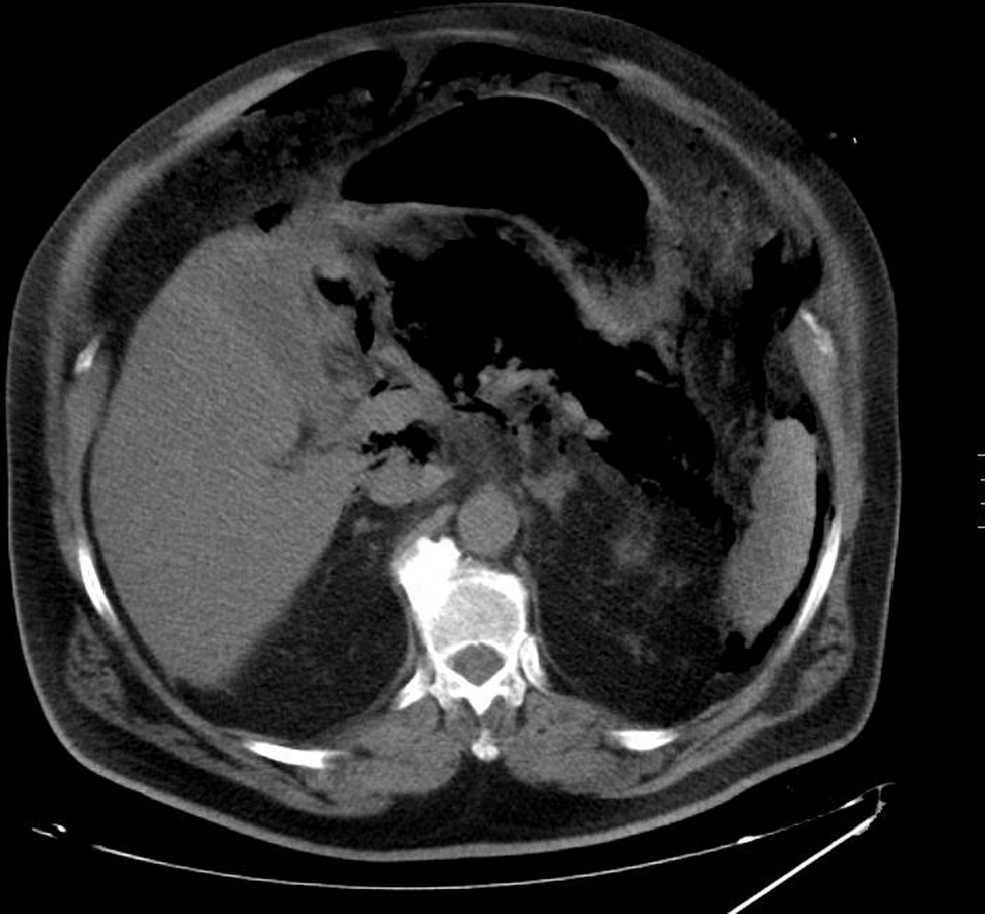

Figura 1. Tomografía computarizada abdominal: pancreatitis enfisematosa, neumoperitoneo y retroneumoperitoneo.

Varón de 66 años, con antecedentes de: obesidad, HTA, diabetes mellitus tipo 2, ex fumador, síndrome de apnea obstructiva del sueño con espirometría con patrón mixto, herniorrafia inguinal, hiperplasia benigna de próstata, HDA por úlcera prepilórica y pancreatitis litiásica leve. Acude por dolor abdominal intenso, de 2h de evolución, de inicio brusco en hemiabdomen superior, que no cede con analgésicos y se acompaña de vómitos. Mantiene buenas constantes vitales (presión arterial, 130/80mmHg; frecuencia cardíaca, 96lat/min; frecuencia respiratoria 20/min, y temperatura, 36°C). En la analítica destacan 18.000 leucocitos; amilasa, 5.900; AST, 169; ALT, 105, y BT, 2,5g/dl; PCR, 0,8. En la ecografía abdominal se visualiza una vesícula distendida con barro biliar sin dilatación de la vía biliar. No se observa bien el páncreas, pero se ve aumentado de tamaño e hipoecoico. Tras 12h, empeora súbitamente su estado clínico, con agitación, sudor, taquipnea, livideces y agudización del dolor abdominal (presión arterial, 90/60mmHg; frecuencia cardíaca, 160lat/min). En la analítica presenta 15.500 leucocitos; glucosa, 332mg/dl; creatinina, 1,7mg/dl; PCR, 6,8mg/dl y acidosis metabólica. El abdomen está distendido sin peritonismo. Su situación clínica se agrava con hipotensión, mala perfusión periférica, bradicardia extrema y asistolia que precisa RCP. Hay deterioro analítico: leucocitos, 4.470; creatinina, 2,5mg/dl; pH 7,23, y bicarbonato, 10,9mmol/l, y precisa noradrenalina a altas dosis (30) y FiO2 al 100%. Se realiza tomografía computarizada abdominal, en la que se observa NP, RNP y gas en el páncreas (figura 1). Ante la sospecha de pancreatitis y perforación de víscera hueca, se decide intervención urgente, en la que no se observa perforación, sino un páncreas necrótico, hemorrágico y desestructurado circundado por un líquido serohemático maloliente. Se realiza colecistectomía, necrosectomía limitada, se colocan drenajes para lavados (Beger). En el líquido citado crece Kleibesella pneumoniae. El paciente se mantiene inestable, en anuria y fallece a las 24h.

La tomografía computarizada abdominal es la técnica de elección en las infecciones enfisematosas del páncreas, ya que detecta el gas en el parénquima pancreático, evalúa su extensión y su localización1,3,4, y también permite detectar colecciones peripancreáticas o gas portal. El contraste intravenoso no es necesario para visualizar el gas, pero es útil para evaluar la necrosis pancreática1. Es importante destacar que aproximadamente un 20% de las necrosis pancreáticas infectadas muestran pequeñas ampollas de gas peripancreático y su presencia aislada no es específica de infección, ya que puede deberse a fístulas entéricas, infarto pancreático, reflujo duodenal tras esfinterotomía o manipulaciones instrumentales endoscópicas1,4,6,8. Una gran cantidad de gas sí es indicativa de PE8. La presencia de gas retroperitoneal en los pacientes con pancreatitis aguda grave es muy infrecuente (2,7%)2. La ecografía en la PE tiene una utilidad limitada. El gas se observa como focos múltiples irregulares ecogénicos con sombra sucia acústica posterior1.